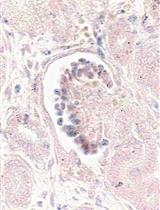

Figure 1. Schematic of liver organoid differentiation protocol. (A) Schematic overview of the differentiation method for liver organoids. (B) Phase-contrast images of iPSCs-HLO depicting change in cell morphology. Scale bar = 100 µm. (C) Reverse transcription qPCR analysis of represented genes related to pluripotency or undifferentiated state and (D) definitive endoderm (DE) state and hepatic function. Undifferentiated iPSCs (iPSCs, n = 3), DE (n = 3), posterior foregut spheroid (foregut, n = 3), and HLO (n = 3). Data are presented as mean ± SEM (n = 3) and analysed by Student t-tests and one-way analysis of variance (ANOVA) using Dunnett’s multiple comparison as a post-hoc test. p < 0.05*, p < 0.001**, and p < 0.0001***.